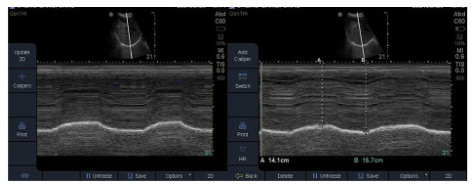

1.4 研究方法达到撤机标准的患者采用T管法行SBT 30 min后进行膈肌超声检查并记录参数。因右侧膈肌肝窗大、受心脏及胃肠气体影响小,便于超声监测时测量,且重复性高,故本项研究选用右侧膈肌超声进行评估,监测期间患者床头抬高取半坐位(30~45°),使用美国索诺声Series S-ICUTM型号超声仪行膈肌超声检查,膈肌超声检查方法:选择凸阵探头(3.5 MHz)沿右侧锁骨中线逐一肋间探查至肋弓下缘交界处,将超声探头向患者背部及头侧倾斜,在B超模式显示出肝脏及膈顶,切换为M超模式,将膈肌运动显示清晰后取样线与长轴形成30°内的夹角并指向膈肌顶部,该切面可进行膈肌移动度(diaphragm excursion, DE)测量(图 1)与计算膈肌RSBI(diaphragmatic-RSBI, D-RSBI=RR/DE)。为减少系统误差,膈肌超声检查指定通过重症超声培训资质的同一名医师执行,共测量3个呼吸周期取平均值。将高频线阵探头(10 MHz)放置在患者腋中线与肋弓交界区9~10肋间后,调整探头平行于肋间隙扫查,当出现2条平行的高回声线时,2条线之间的低弱回声即为膈肌,监测膈肌随呼吸周期运动其厚度发生变化,将膈肌显示清晰后可测量吸气末膈肌厚度和呼气末膈肌厚度(图 2)。参照程滔等[15]研究共测量3个呼吸周期取平均值, 可计算膈肌厚度变化率(diaphragm thickening fraction, DTF)=(吸气末膈肌厚度-呼气末膈肌厚度/呼气末膈肌厚度)×100%。

| M超模式下膈肌随呼吸运动曲线,DE=吸气末膈肌运动幅度-呼气末膈肌运动幅度。 图 1 膈肌移动度 Fig 1 Diaphragm excursion |